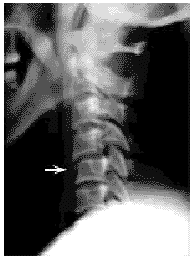

男,53岁,高处坠落致头颈部损伤,四肢活动障碍2 d入院。查体:患者神志清楚,四肢不全瘫。X线片示:C5椎体前上缘骨折,C4,5半脱位(图1),MRI示:C4,5椎间盘稍膨出,脊髓在C4,5椎体平面有挫伤变性。MRA扫描发现右侧椎动脉完全无血流成像,C5水平常规MRI T2横断面上,右侧椎动脉内可见到高信号血栓影像(图2~3),确诊为右侧椎动脉损伤。

图1 C5前上缘骨折,C4,5半脱位